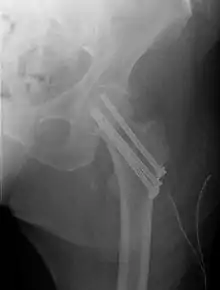

A hip fracture is a break that occurs in the upper part of the femur (thigh bone), at the femoral neck or (rarely) the femoral head.[2] Symptoms may include pain around the hip, particularly with movement, and shortening of the leg.[2] Usually the person cannot walk.[3]

| Intertrochanteric hip fracture in a 17-year-old male | |

Closed reduction may not be satisfactory and open reduction then becomes necessary.[42] The use of open reduction has been reported as 8-13% among pertrochanteric fractures, and 52% among intertrochanteric fractures.[43] Both intertrochanteric and pertrochanteric fractures may be treated by a dynamic hip screw and plate, or an intramedullary rod.[42]

The fracture typically takes 3–6 months to heal. As it is only common in elderly, removal of the dynamic hip screw is usually not recommended to avoid unnecessary risk of second operation and the increased risk of re-fracture after implant removal. The most common cause for hip fractures in the elderly is osteoporosis; if this is the case, treatment of the osteoporosis can well reduce the risk of further fracture. Only young patients tend to consider having it removed; the implant may function as a stress riser, increasing the risk of a break if another accident occurs.